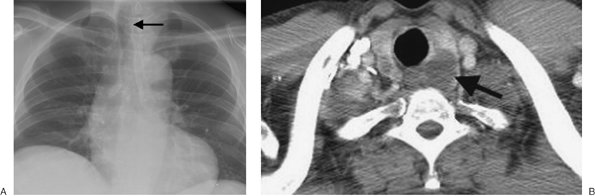

FIGURE 6-7. Thyroid goiter. A: PA chest radiograph shows a left paratracheal mass and deviation of the trachea to the right (arrow). B: CT scan shows a heterogeneous left thyroid mass with cystic components (arrow). There is also a smaller cyst within the right lobe.